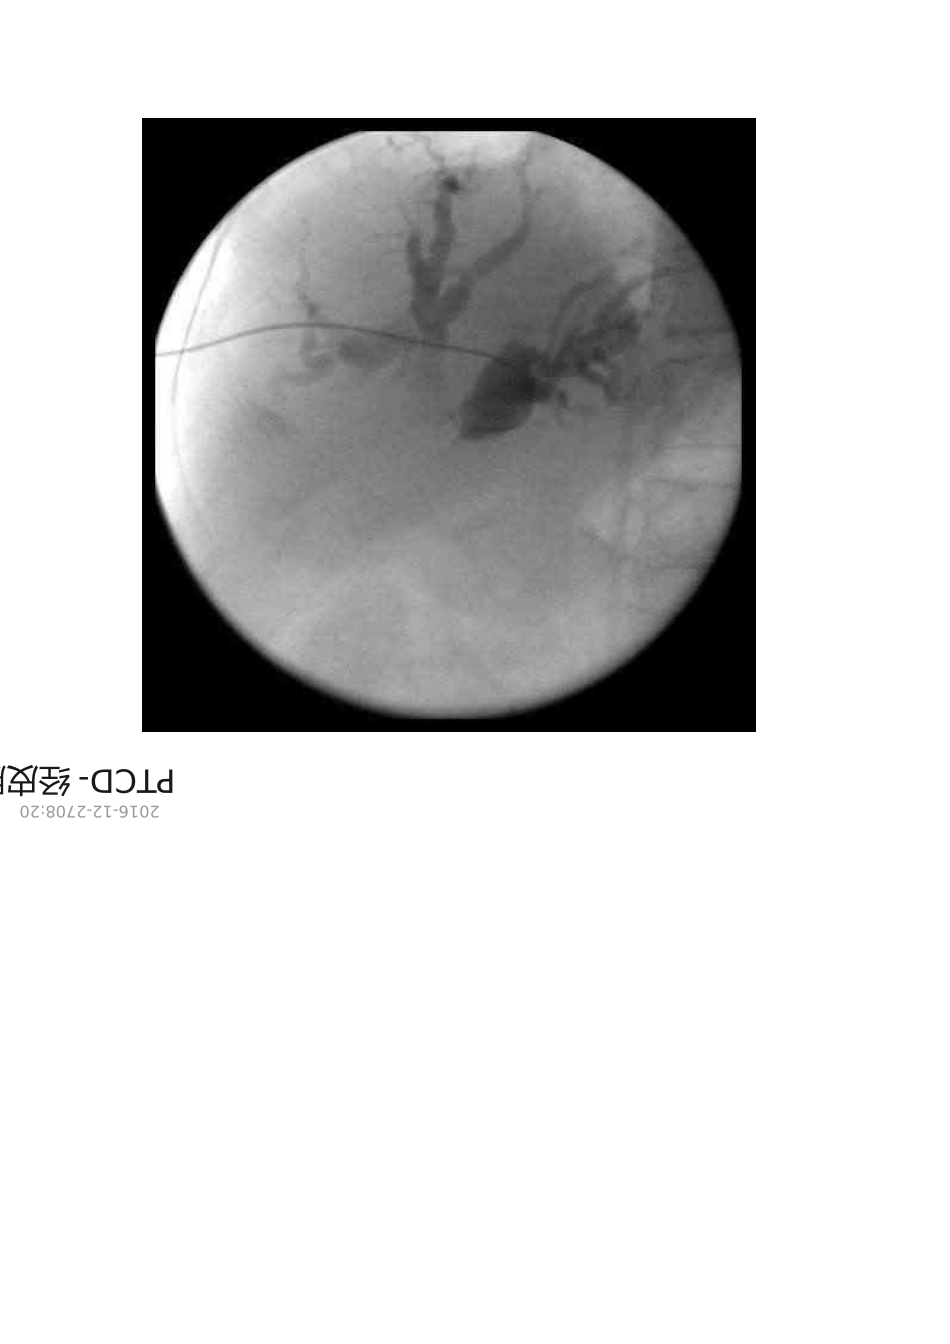

PTCD- 经皮肝穿胆道引流术2016-12-2708:20崔彦教授解放军306 医院普外科恶性梗阻性黄疸被发现时多已晚期据统计其中只有7% 能作外科根治术姑息分流旁路术也仅适用于其中 19% 得病例。临床为改善恶性梗阻性黄疸患者症状、提高生活质量与延长生命经皮穿肝内胆管引流术 PTCD 及胆管内支架置放术有较好作用。经皮肝穿胆道引流术 percuteneoustranshepaticcholangiodrainagePTCD 就是指在影像设备通常为DSA 下 X 线透视或 B 超引导下经皮经肝穿刺胆管并置入引流管使胆汁流向体外或十二指肠得一系列技术。主要用于胆道梗阻与急性炎症得治疗。包括外引流、内引流与内外引流就是所有胆道梗阻介入治疗得基本技术。外引流当引流管不能或不必通过梗阻部位将胆汁引流至体外引流袋。肝门部梗阻或化脓性胆管炎可多支引流。内外引。适合手术得有 1 、手术不能切除得恶性梗阻性黄疸如胰腺癌。2 、原发性胆系恶性肿瘤以及肿瘤已侵犯到肝门部胆管汇与处。3 、中晚期肝癌造成得梗阻性黄疸。 4 、肝门区转移性肿瘤、肿大淋巴结压迫胆总管。 5 、各种因素致使外科手术危险性大不易手术者。如年老体弱心肺功能不全等。6 、外科手术前作暂时引流以改善全身状况为手术作准备。禁忌手术得情况有 1 、凝血机制差凝血酶原时间低于 70% 。 2 、脓毒血症。 3 、大量腹水。 4 、终末期病人。流导丝顺利通过梗阻进入十二指肠采用内外引流管将胆汁引流至肠道。通常外引流通道为关闭状态留作冲洗与后续治疗用一、引导设备1 、 DSA 下 X 线透视传统仍然就是主要手段。优点引导手术全过程可实时动态监视导管、导丝得走向。缺点辐射损害、需要盲目试穿。2 、 B 超引导优缺点与上相反。3 、 B 超透视 B 超引导胆管穿刺可视性与准确性好后续操作透视得优点可发挥。缺点设备依赖性强。二、适应证与禁忌证1 、适应证1 、 1 晚期肿瘤引起得恶性胆道梗阻行姑息性胆道引流。1 、 2 深度黄疸病人得术前准备包括良性与恶性病变。1 、 3 急性胆道感染如急性梗阻性化脓性胆管炎行急症胆道减压引流使急症手术转为择期手术。1 、 4 良性胆道狭窄经多次胆道修补胆道重建及胆肠吻合口狭窄等。1 、 5 通过引流管行化疗、放疗、溶石、细胞学检查及经皮行纤维胆道镜取石等。2 、禁忌证2 、 1 对碘过敏有严重凝血机能障碍、初学倾向严重...